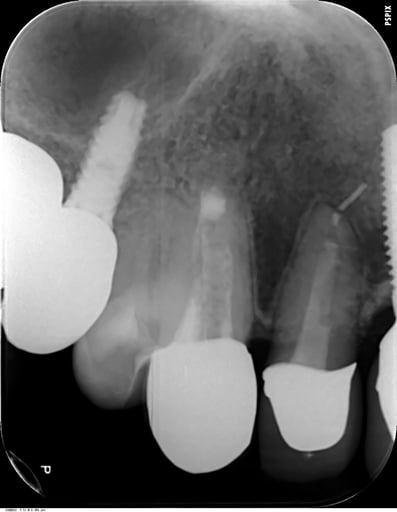

#インプラント